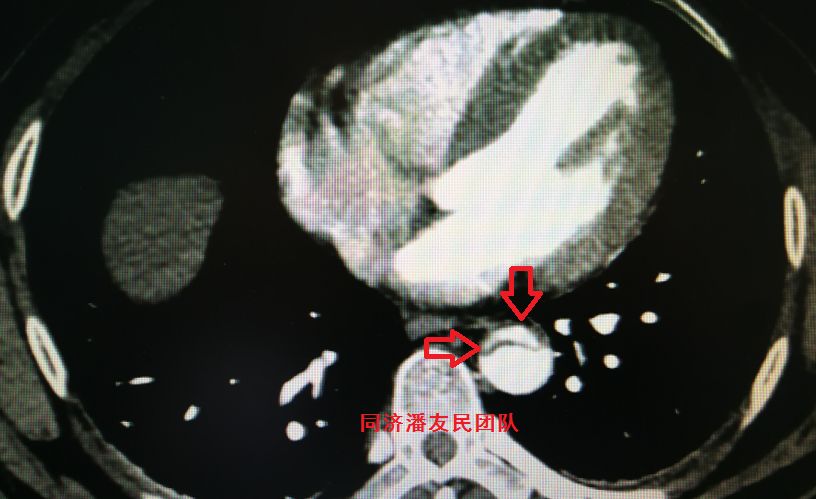

结果在上级医院复查胸腹主动脉CTA,在平扫CT提示主动脉夹层的对应层面,证实了主动脉夹层(图3~6)。同时发现升主动脉及主动脉弓均有夹层撕裂 (图7~8) 。 因此,正确诊断应该是 A型 (1型) 主动脉夹层。

图5:平扫CT显示腹主动脉段血管钙化点内移征(红箭头所示)

图6:CTA显示图5相应层面,钙化点内移征及夹层撕裂内膜片(红箭头所示)